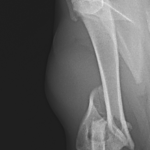

上腕骨遠位粉砕骨折

若い猫ちゃんが部屋で遊んでいたところ、不運にも上腕骨を粉砕骨折してしまったとのこと。かかりつけ医から固定術の依頼がありました。粉砕部分をOrthogonal Plateで固定術を行いました。